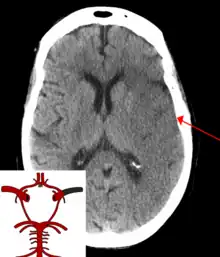

CT scan of an intraparenchymal bleed (bottom arrow) with surrounding edema (top arrow)

There are two main types of hemorrhagic stroke:[28][29]

The above two main types of hemorrhagic stroke are also two different forms of intracranial hemorrhage, which is the accumulation of blood anywhere within the cranial vault; but the other forms of intracranial hemorrhage, such as epidural hematoma (bleeding between the skull and the dura mater, which is the thick outermost layer of the meninges that surround the brain) and subdural hematoma (bleeding in the subdural space), are not considered "hemorrhagic strokes".[30]

Hemorrhagic strokes may occur on the background of alterations to the blood vessels in the brain, such as cerebral amyloid angiopathy, cerebral arteriovenous malformation and an intracranial aneurysm, which can cause intraparenchymal or subarachnoid hemorrhage.